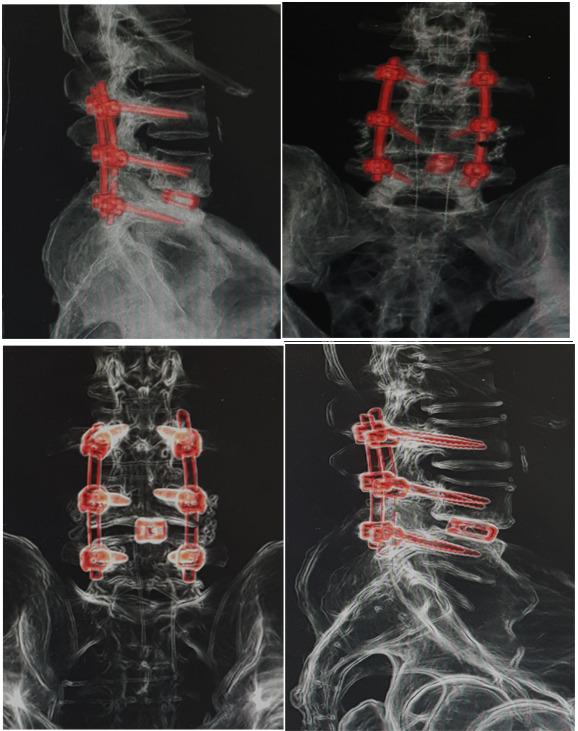

وقد تكللت العملية ولله الحمد بالنجاح- وتمكّن المريض ولأول مرة منذ عامين المشي والحركة بدون ألم أو تنميل في الأطراف السفلية، حيث تم خلال العملية تثبيت الفقرات القطنية بواسطة مسامير تيتانيوم مع تركيب قفص تيتانيوم (إلمانية الصنع)، بهدف رفع الضغط عن جذور الأعصاب وتوسيع القناة العصبية القطنية وتوسيع مخارج جذور الأعصاب.